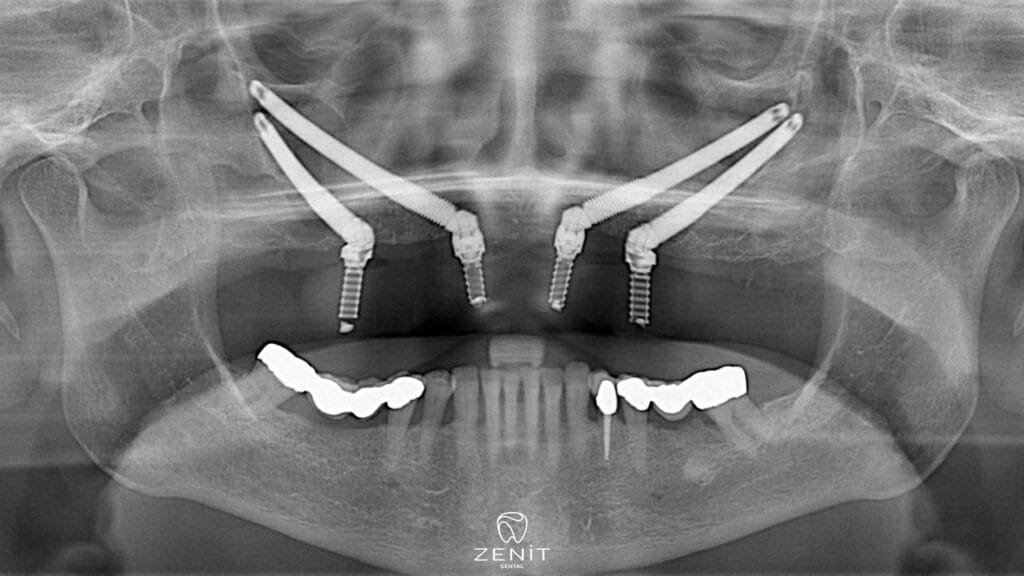

Zygoma-Implantate bieten eine hervorragende Alternative für Patienten mit unzureichendem Kieferknochen und bieten eine revolutionäre Behandlung im Gesichtsbereich. Diese speziellen Implantate werden im Gegensatz zu herkömmlichen Implantaten in den Jochbeinknochen (Zygoma) und nicht in den Oberkieferknochen eingesetzt. Da der Jochbeinknochen eine dichtere und stärkere Struktur aufweist als der Kieferknochen, können Jochbeinimplantate in diesem Bereich sicher eingesetzt werden. Dank Zygoma-Implantaten können auch Patienten mit fortgeschrittenem Knochenschwund ästhetisch und funktionell zufriedenstellende Ergebnisse erzielen.

Zygoma-Implantate, die im Wangenknochen eingesetzt werden, werden im Gegensatz zu anderen Zahnimplantaten nicht im Kieferknochen, sondern im Bereich des Jochbeins platziert, der sich in der Mitte des Gesichts befindet und eine sehr solide Struktur aufweist. Der Jochbeinknochen hat eine dichtere Struktur als andere Knochen und Knochenverlust tritt normalerweise nicht auf. Dank dieser Funktion bieten Zygoma-Implantate eine sichere und wirksame Lösung für Patienten mit Kieferknochenmangel.

- Implantatinsertion: Zygoma-Implantate werden im Wangenknochen statt im Oberkieferknochen eingesetzt. Beim Einsetzen der Implantate arbeitet der Chirurg mit hoher Präzision, denn das Erreichen des Jochbeinbereichs und das Einsetzen der Implantate in die richtige Position erfordert große Sorgfalt.